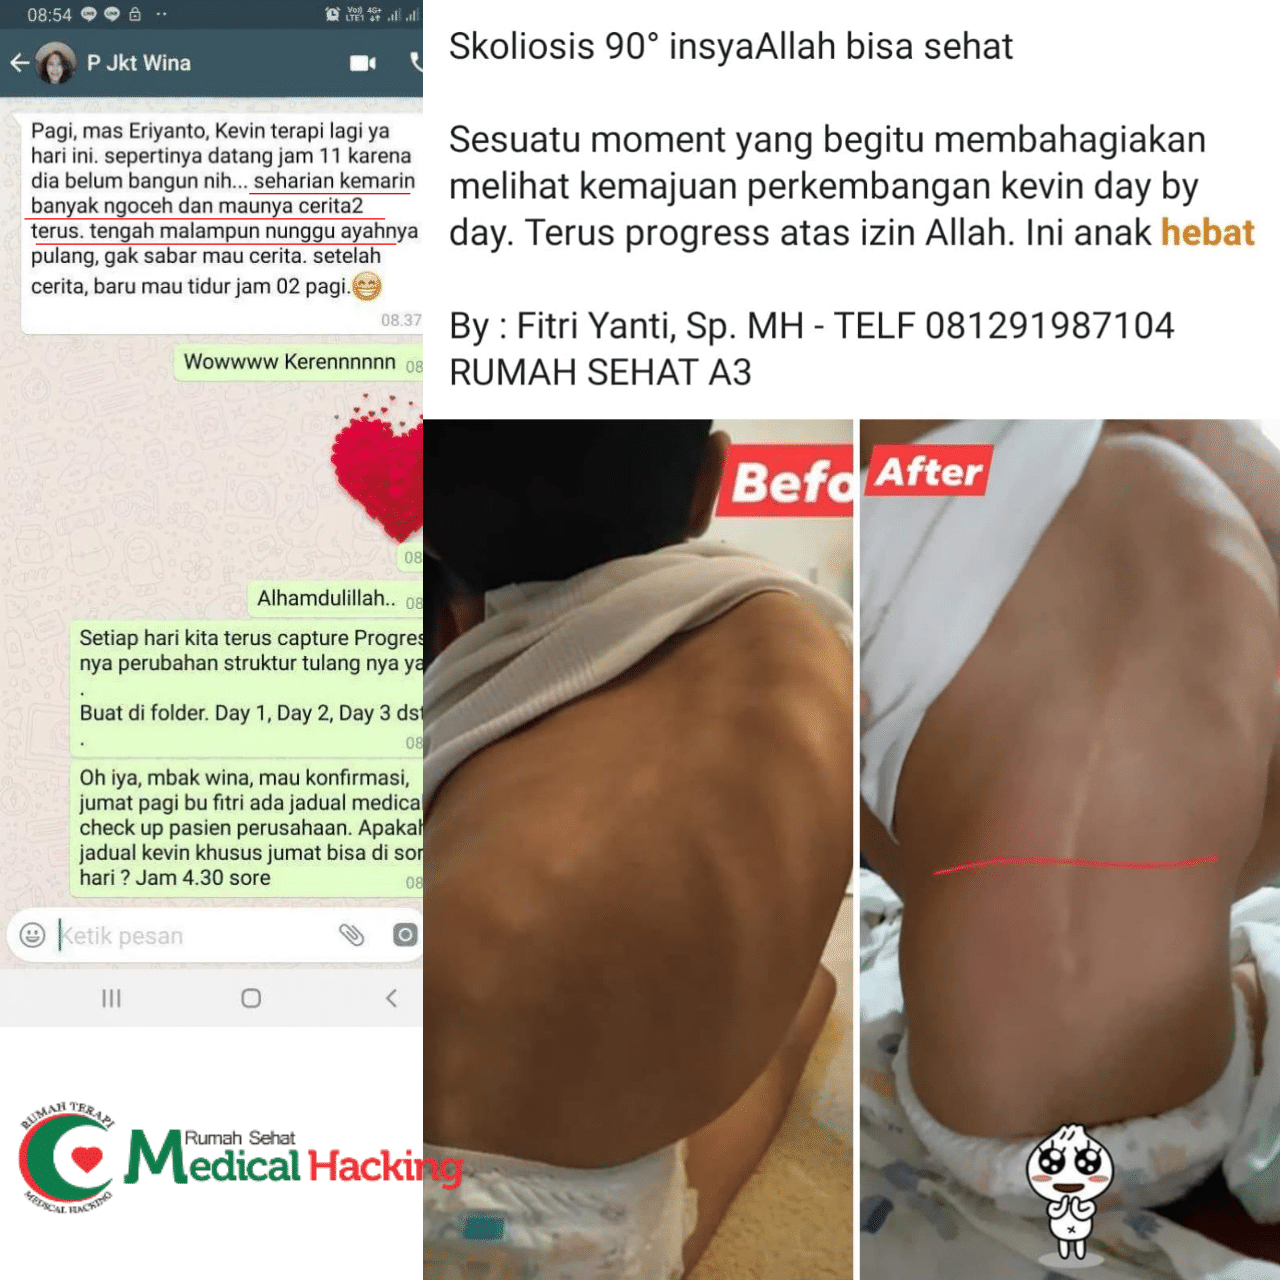

Anda boleh mencari tempat medis, namun kami ada pengobatan non medis yang merupakan tempat terapi yang ahli menangani masalah infeksi tulang. Selain itu kami merekomendasikan tempat terapi saraf dan sendi di Tangerang, yang ahli menangani masalah hal ini.

Simak artikel ini hingga selesai, karena kami mengulas beberapa hal. Termasuk kami merekomendasikan pengobatan alternatif, berupa tempat terapi agar Anda melakukan aktivitas terbebas dari infeksi tulang.

Jika Anda sedang berobat menggunakan jalur medis, tidak menjadi masalah. Di awal artikel yang Anda baca saat ini, kami menyarankan mengobati jalur non medis sebagai pendamping.

Medical Hacking yang merupakan satu-satunya tempat terapi untuk meminimalisir hingga mencegah dari infeksi tulang.